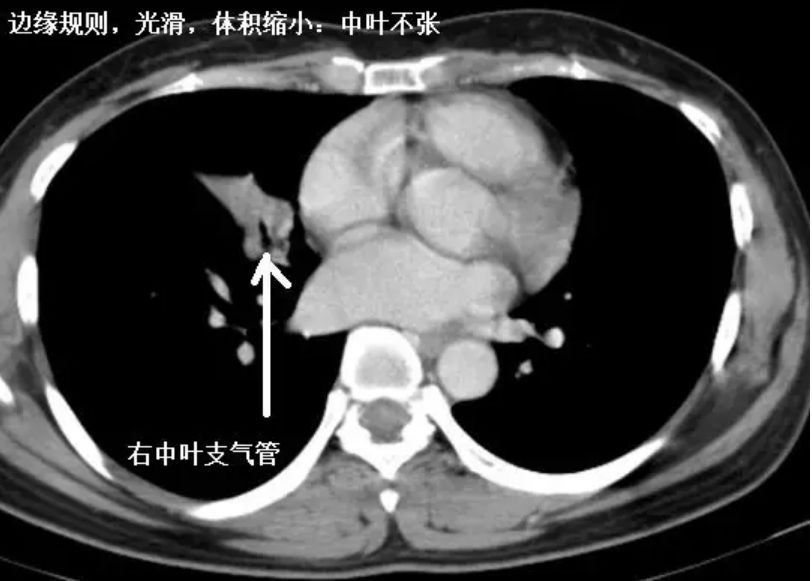

肺与纵隔-常见疾病课件.ppt

图片尺寸1152x864